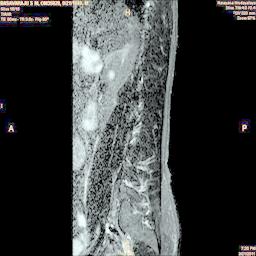

The developed algorithm presented in the previous section was coded using Matlab Version 8.0. The experiment was conducted by considering poor quality spinal cord images of having various lesions. The first column of Fig. 4 shows the axial view of neck spinal cord images of size pixels, respectively. The second column of Fig. 4 presents the same images enhanced using histogram equalization. As is evident from the results presented, the histogram equalization method performs global image enhancement operation which improves the contrast of an image but at the cost loss in image details. The third column of Fig. 4 shows the MSR based spinal cord image enhancement. It can be seen that from the result presented, MSR scheme improves the details that are not clearly visible in histogram equalization technique. In general, image enhancement achieved by MSR method is better compared to histogram equalization. However, the MSR method voilates gray world assumption. Therefore, the image enhanced by this scheme appears to be grayish. Although, numerous work have been reported for solving the problem due to gray world voilation, no work seems to developed for complete elimination.

The fourth column of Fig. 4 shows the image enhanced using Chao et al. []. It can be seen from the results presented that the reconstructed images of Chao’s method have black spots. The appearance of these dark patches degrades the visual quality of the enhanced image. The image enhanced using proposed multirate multiscale retinex image enhancement method presented in the fifth column of Fig. 4, overcomes the drawback of the Chao’s method. As we can see from the simulation results, image enhancement achieved by the proposed method has improved details with significant contrast enhancement. The enhanced images from the proposed method provides information to physicians, radiologists and researchers for various types of pathology detection.